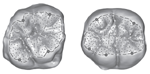

Three-Dimensional Analysis of Posterior Mandibular Displacement in Rats. Lyros I, Ferdianakis E, Halazonetis D, Lykogeorgos T, Alexiou A, Alexiou K-E, Georgaki M, Vardas E, Yfanti Z, Tsolakis AI. Vet Sci 2022;9,144. doi: 10.3390/vetsci9030144. PMID: 35324872.